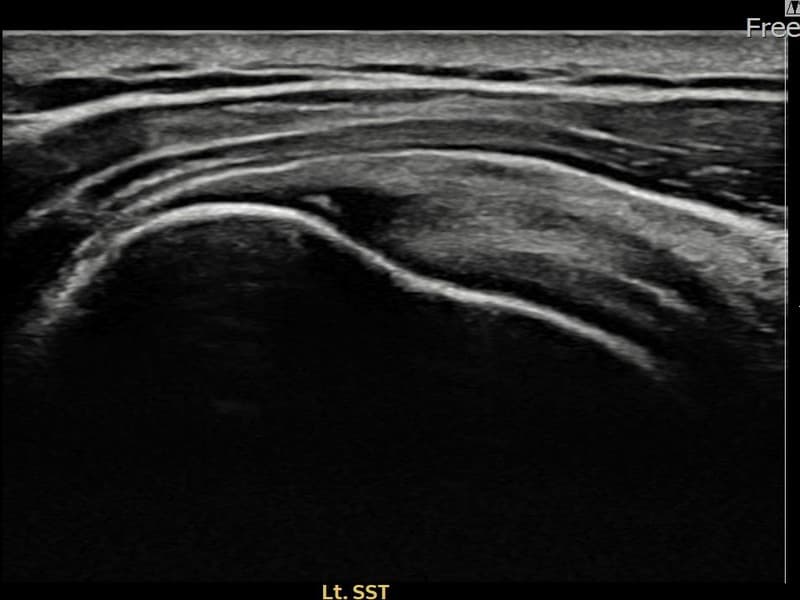

시술 전 초음파 측정 결과 파열 크기는 9mm × 4mm (힘줄 두께의 약 38% 결손)로 확인되었습니다. 시술 전 초음파에서 좌측 극상근건 부착부의 뚜렷한 에코 단절과 힘줄 결손 소견이 확인되었습니다. 시술 후 초음파에서 부착부 연속성이 회복되고 결손 부위에 재생 조직이 형성된 것이 관찰되었습니다.

60대 중반 남성 환자분으로, 왼쪽 어깨 통증이 6개월 이상 지속되어 내원하셨습니다. 은퇴 후 농작업을 하시면서 반복적으로 팔을 들어 올리는 동작을 많이 하셨고, 처음에는 무거운 것을 들 때만 아프다가 점점 팔을 조금만 들어도 통증이 심해지는 상태로 진행되었습니다. 초음파 검사에서 좌측 극상근건 부착부 부분파열이 확인되었으며, 초음파 유도 하 축소봉합술을 시행하였습니다. 시술 후 단계적 재활 운동을 통해 꾸준히 회복을 진행하였고, 시술 10주 후 추적 초음파에서 부착부 힘줄 연속성이 완전히 회복된 것이 확인되어 정상 생활에 복귀하셨습니다.